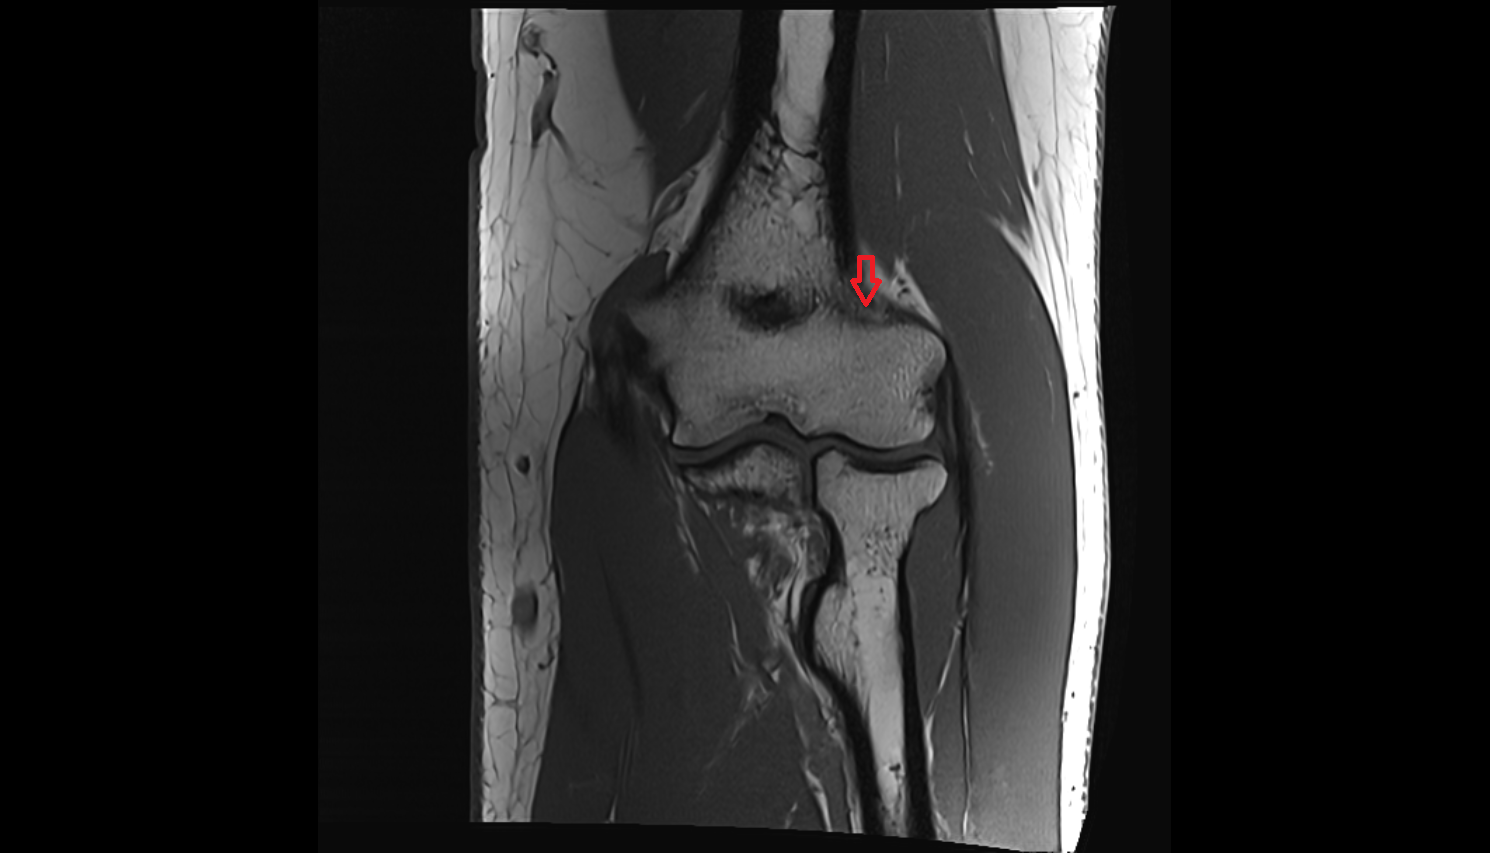

- Knee Joint